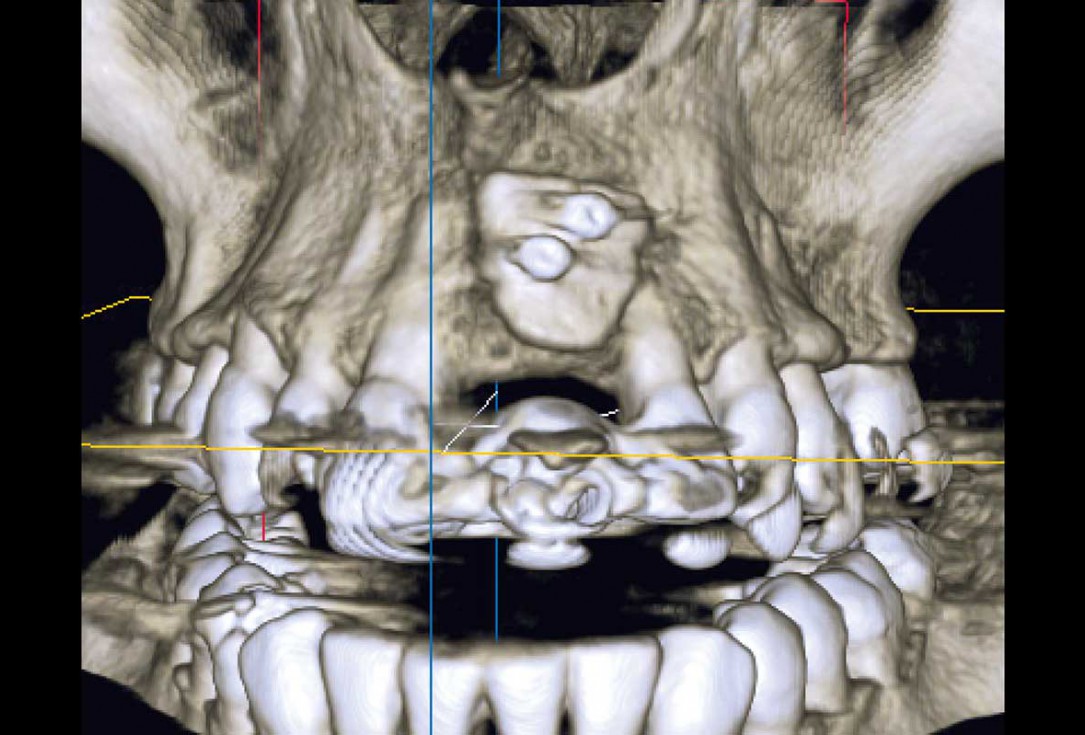

3/35 - CBCT: Advanced bone loss after traumatic tooth loss more than 10 years agoBlock grafting in the aesthetic zone with maxgraft®, Jason® membrane and cerabone® - Dres. H. Maghaireh and V. Ivancheva

4/35 - Patient used to have a diastema in the area which she no longer wanted to be recreated. Treatment plan: implant for UL1 and a veneer for the UR1 to match the space analysis and achieve acceptable and symmetrical aesthetic outcomeBlock grafting in the aesthetic zone with maxgraft®, Jason® membrane and cerabone® - Dres. H. Maghaireh and V. Ivancheva